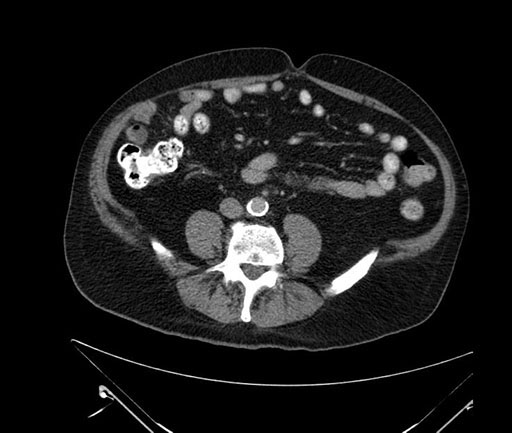

Axial - 3 months prior

Imaging analysis